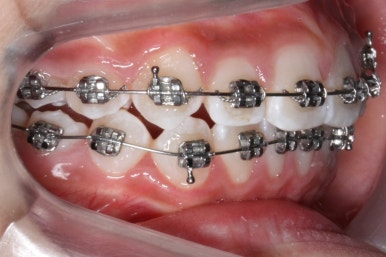

아래쪽에도 이제 장치를 전부 부착했습니다.

한 쪽의 송곳니는 제위치로 벌써 자리를 잡았네요.

장치를 부착한 후에 순차적으로 변화가 나타나는 모습입니다.

총 4장의 사진 동안 경과한 시간은 불과 6개월 입니다. 헤드기어를 통해 사전에 작업을 해뒀기 때문에 이후 연산동덧니교정 과정은 편해진 것이죠.